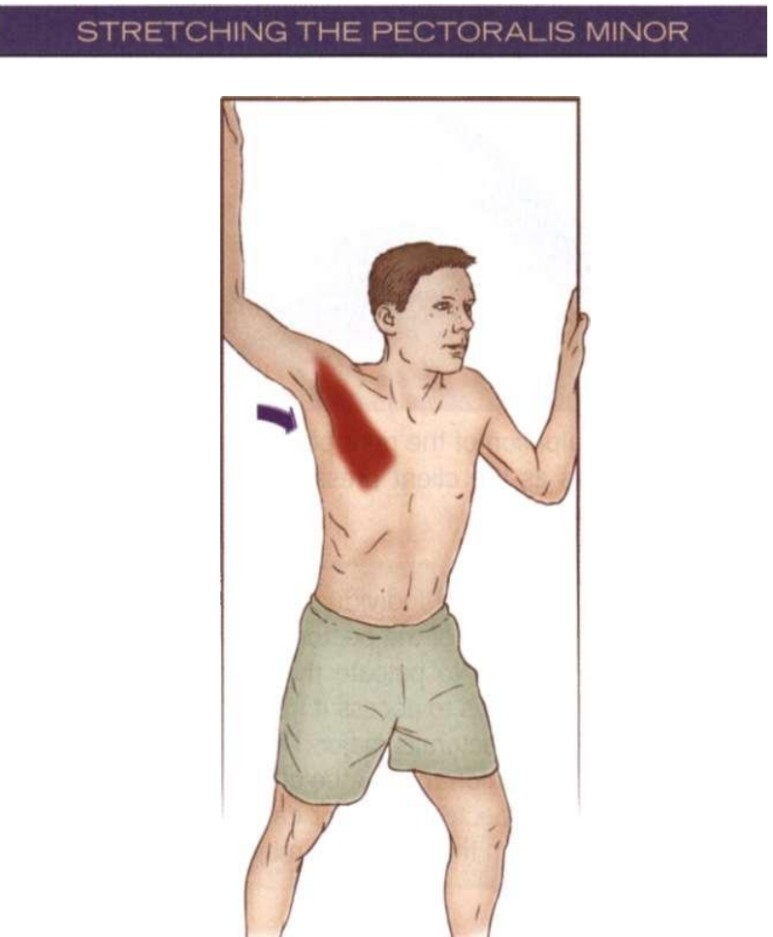

스트레칭 / Stretching

<소흉근/작은가슴근 스트레칭>

· 소흉근/작은가슴근 스트레칭은 대흉근/큰가슴근 스트레칭과 매우 유사합니다.

팔을 벌림(abduction)시킨 자세로 대략 135도로 벌린 후 문에 기대어 늘려줍니다.